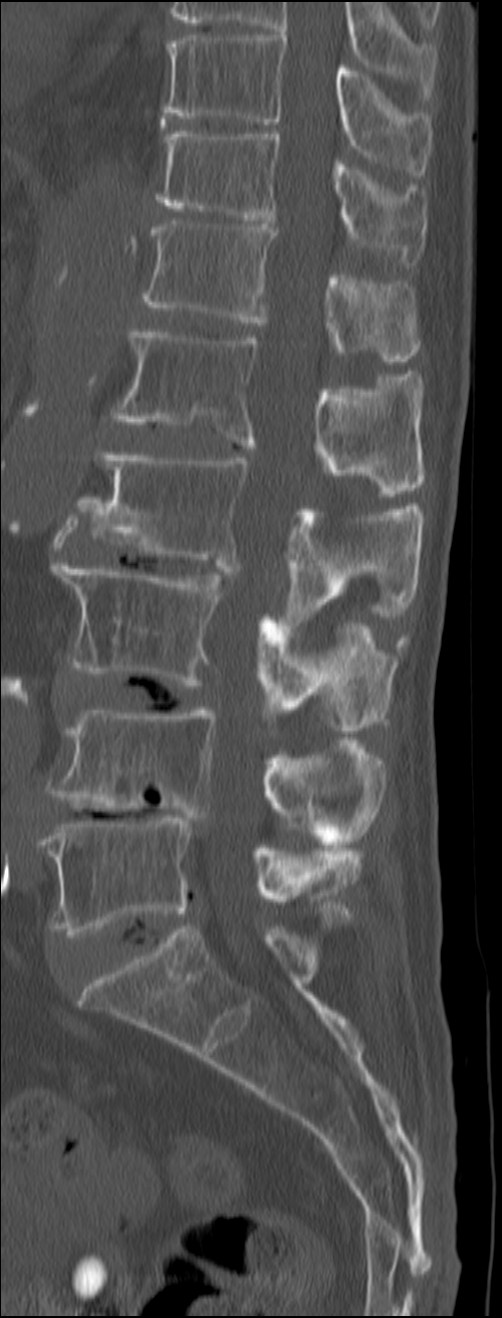

整形領域

MR禁忌や体動のある患者への対応

DE Bone Marrowは、DECT画像から骨髄浮腫の有無を評価することができる。検査時間も短いため体動による画質低下も少なく、新鮮骨折と陳旧性骨折の鑑別を簡便に行うことが可能である。本症例では、DE Bone MarrowとMRIの異常所見は一致しており、DE Bone Marrowの正確性を表していると思われる。DE Bone Marrowは整形外科からの評価も高く、椎体圧迫骨折の評価において、DECTが第一選択となっている。